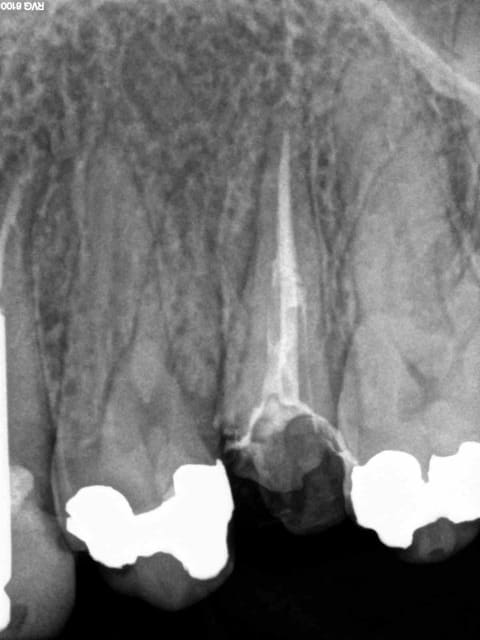

Souvent il n'y a rien, c'est plus facile. On peut d'ailleurs illustrer en quasi direct ses propos tellement c'est fréquent. Cas tous frais.-)))))

1 bd9s5w - Eugenol

2 c9r7kc - Eugenol

3 wheqza - Eugenol

4 ass1cx - Eugenol

Encore un cas plus frais que le précédent, on innove cone sans pate cette fois ci ( ou la moitié du canal en 8 d'obturé. -)))

1 nhq0pn - Eugenol

2 l2h3ce - Eugenol

3 nnbzcw - Eugenol

4 wnkfxu - Eugenol